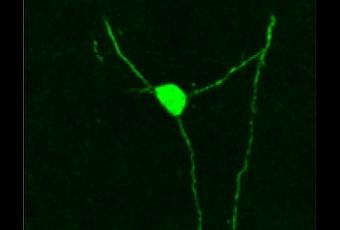

Ces neurones naissant ont survécu au processus de transplantation et se sont correctement intégrés dans les circuits. Les chercheurs expliquent que ces neurones récemment développés communiquent avec les autres neurones par contacts synaptiques, et que le cerveau, à son tour, émet un signal en retour. En réponse à la leptine, à l'insuline et au glucose, ces neurones ont effectivement rejoint le réseau du cerveau et recablé les circuits endommagés. L'un des auteurs explique : « Je suis frappé qu'un nombre relativement restreint de neurones génétiquement normaux puisse réparer efficacement les circuits. "